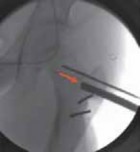

16. On the AP image the guide pin needs to be sufficiently proximal (superior) to provide enough room to permit the introduction of the seating chisel inferior to the guide pin (

TECH FIG 2A

).

17. On the frog-leg lateral view, the guide pin should lie in the middle of the femoral neck in line with the neck axis (

TECH FIG 2B

--- TECH FIG 2 • Intraoperative C-arm–guided insertion of the seating chisel for the blade plate.A. Insertion of the guide pin in the superior part of the neck at right angles to the long axis of the femur. B. Position of the guide pin along the midfemoral neck axis in the frog-leg lateral view. C. Position of the seating chisel parallel to the guide pin and perpendicular to the long axis of the femur. D. Position of the seating chisel parallel to the guide pin and along the midfemoral neck axis on the frog-leg lateral view. E. The seating chisel is backed out from its final position to disimpact the chisel before the osteotomy.Pr FiAE